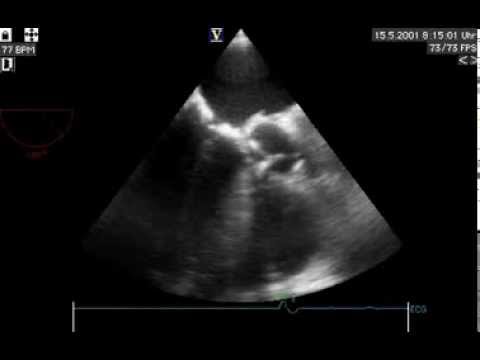

Video 16.1

Video 16.1 Echocardiographic exclusion of alternative cardioembolic sources.